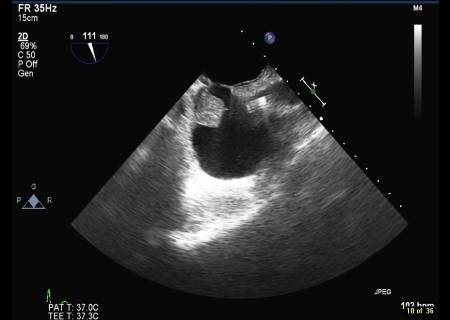

[Figure caption and citation for the preceding image starts]: Transoesophageal echocardiogram showing a catheter in the superior vena cava and a right atrial thrombus (note: not attached to septum)From the collection of Dr Syed Wamique Yusuf, Department of Cardiology, University of Texas MD Anderson Cancer Center; used with permission [Citation ends].

Echocardiogram or MRI/CT scan will reveal the thrombus. Echocardiogram will also identify the catheter that is commonly associated with the formation of the thrombus. Rarely a transvenous biopsy may be indicated.